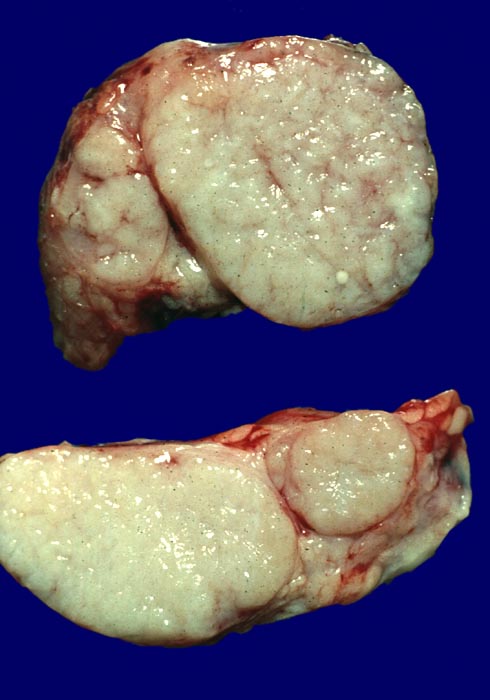

Makroskopie

Befund

Pathologischer Befund

Normalbefund